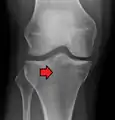

Lateral Tibial Plateau fracture XRay with Depression

• Type II = Lateral tibial plateau fracture with depression,

This is a combined cleavage and compression fracture and involves vertical split of the lateral condyle combined with depression of the adjacent load bearing part of the condyle. Caused by a valgus force on the knee; it is a low energy injury, typically seen in individuals of the 4th decade or older with osteoporotic changes in bone. Most common, and make up 75% of all tibial plateau fractures. There is a 20% risk of distraction injuries to the medial collateral ligament. May include distraction injury to the medial collateral ligament or anterior cruciate ligament.